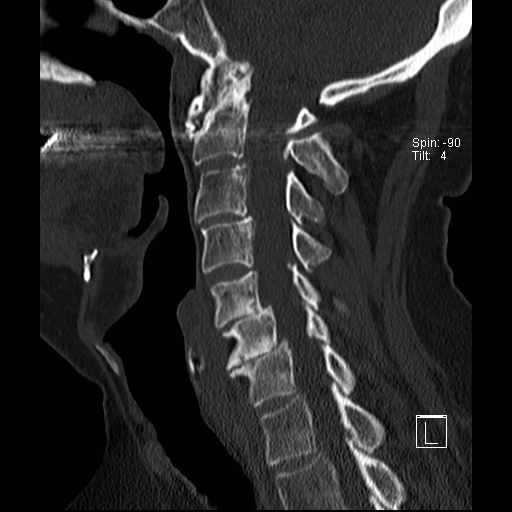

Lồng nền sọ

Lồng nền sọ, còn gọi là sụt lún sọ não hay ấn nền sọ, xảy ra ở 5-10% bệnh nhân viêm khớp dạng thấp cột sống cổ.

Trong lồng nền sọ, mỏm răng sa vào lỗ chẩm làm thu hẹp không gian dành cho tủy sống.

Biểu hiện lâm sàng đa dạng, từ đau đầu mạn tính, hạn chế vận động cổ đến suy giảm thần kinh cấp tính (chèn ép tủy sống và thân não, có thể dẫn đến liệt hoặc thậm chí tử vong nếu cổ bị di chuyển ở một số tư thế nhất định).

Hình ảnh

Cuộn xem các lát cắt CT.

Có hình ảnh di chuyển lên trên của mỏm răng vào lỗ chẩm.